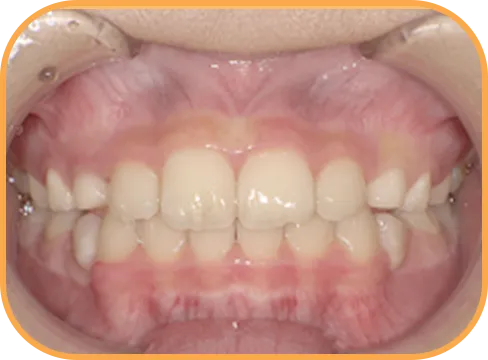

• After

• 正 面

治療後正面からの歯の様子

主 訴

前歯ガタガタ、前歯が大きい

治療内容

インビザライン・ファースト

治療期間

7か月

治療費(税別)

450,000円+診断料5,000円

リスク・副作用

• 親知らずの影響や加齢などによって、凸凹が生じる可能性があります。

• 治療の初期段階では痛みや不快感が生じやすくなりますが、1週間前後で慣れます。

• 顎の成長発育によって、噛み合わせや歯並びが変化する可能性があります。

• 状況により当初予定した治療計画を変更する可能性があります。